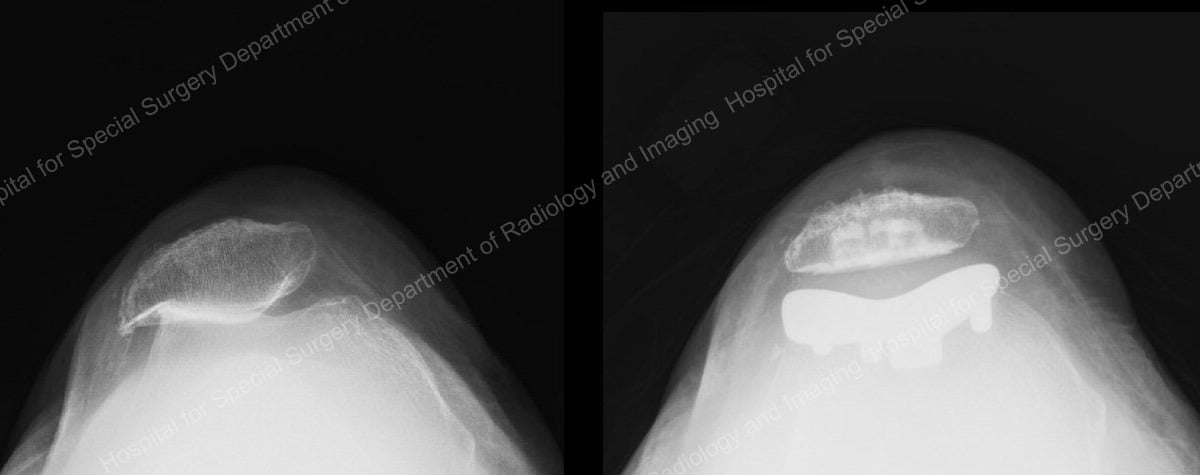

X-rays of patellofemoral arthritis (left) and the joint after patellofemoral knee replacement.